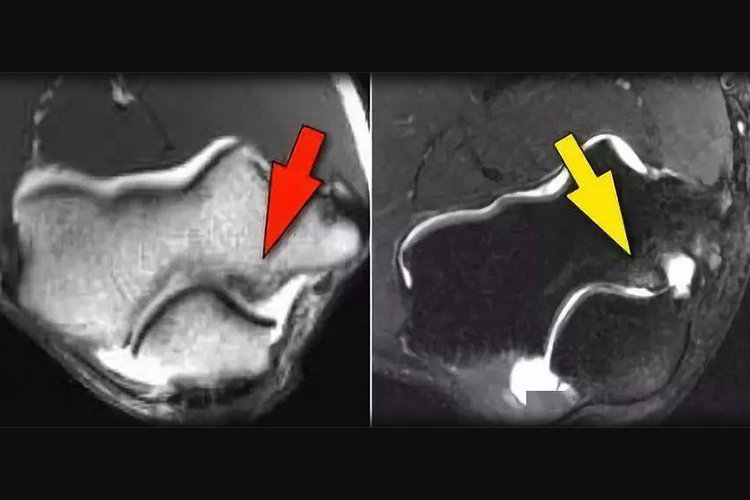

肘关节软骨损伤进行核磁共振检查时,影像结果可见软骨变性,T1加权像显示软骨变形、不规则、信号减低等现象。患者的肘部可伴有出血导致的肿胀、疼痛,运动或受力时,肘关节锁定、滞涩。